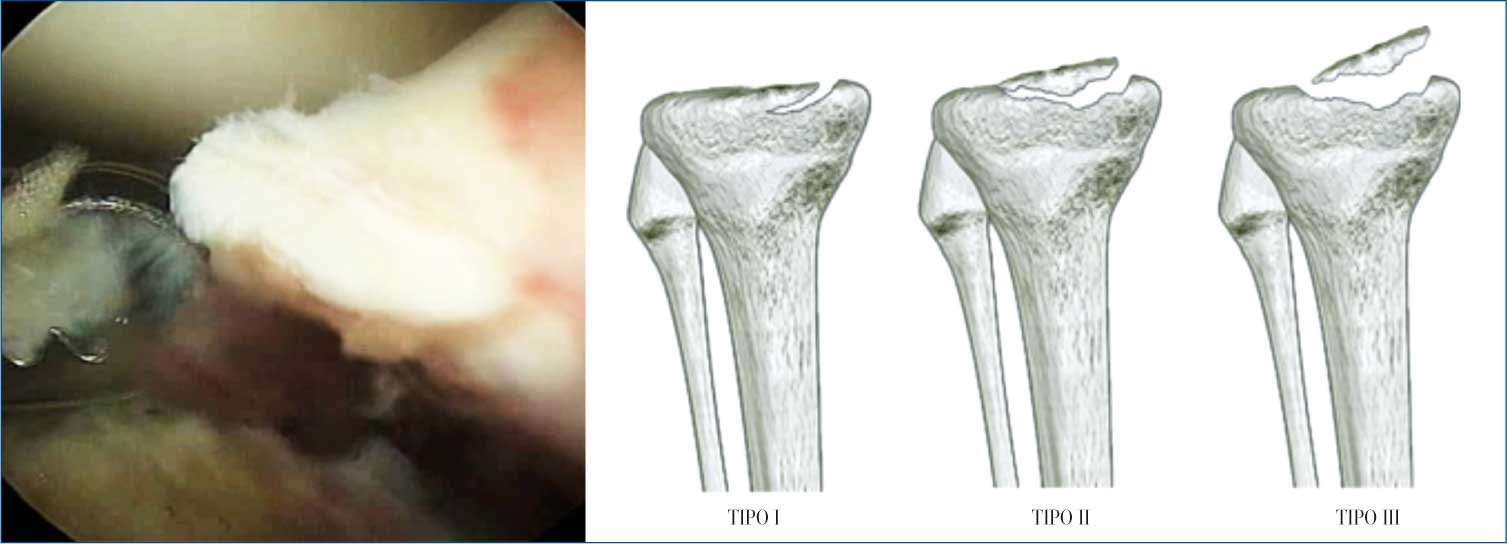

Meyers e Mc Keever (Figura 3) con la loro fondamentale classificazione, hanno contribuito, per primi a differenziare il trattamento a seconda del tipo di frattura ed hanno fortemente condizionato gli altri autori nella scelta terapeutica.

Tipo I con minimo spostamento del frammento avulso;

Tipo II con spostamento del 3° anteriore del frammento avulso “a becco” nella Rx laterale;

Tipo III con completa separazione

del frammento dal pavimento tibiale, senza apposizione di frammenti;

Tipo III + R: uguale al III tipo con l’aggravante della componente rotatoria che rende l’unione più difficile.

Figura 3

Il sottotipo III + R, corrisponde al IV tipo di Zaricznyi (1977) con l’aggiunta della comminuzione.